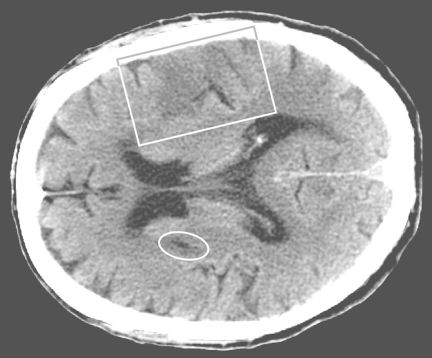

Treatment with tPA saves many patients—as it did Anderson Holness—by opening obstructed blood vessels in their brains. But the drug has severe limitations. Doctors have to first do a computerized tomography scan to make sure that the person isn’t experiencing a bleeding stroke, which tPA would make worse. And the clot-busting drug must be administered within 3 hours of the onset of a stroke—which isn’t always possible because many delays occur on the way to emergency treatment. After 3 hours, the risk of bleeding outweighs the potential benefit of tPA, at least according to current medical judgment. The potential complications have made emergency room physicians reluctant to give tPA, says Costantino Iadecola, chief of the division of neurobiology at Weill Cornell Medical College in New York City.

By now, researchers have a pretty complete understanding of these events, Iadecola says. As soon as blood flow is interrupted, nerve cells in the immediate area of the blockage start dying for lack of oxygen and energy-providing glucose. Most of the cells at the core of a stroke can’t be rescued unless blood flow is reestablished within a few minutes.

The area around the core still has some blood flow and remains salvageable for hours, Iadecola says. But dying cells in the core make matters worse by releasing glutamate, a chemical that normally transmits nerve signals.

In this case, glutamate is dangerous because it triggers brain cells outside the stroke core to open critical pores to an influx of calcium ions. That starts a wave of inflammation, free radical production, and DNA and protein destruction that leads, about a day after the stroke, to the activation of a cell-suicide program called apoptosis.